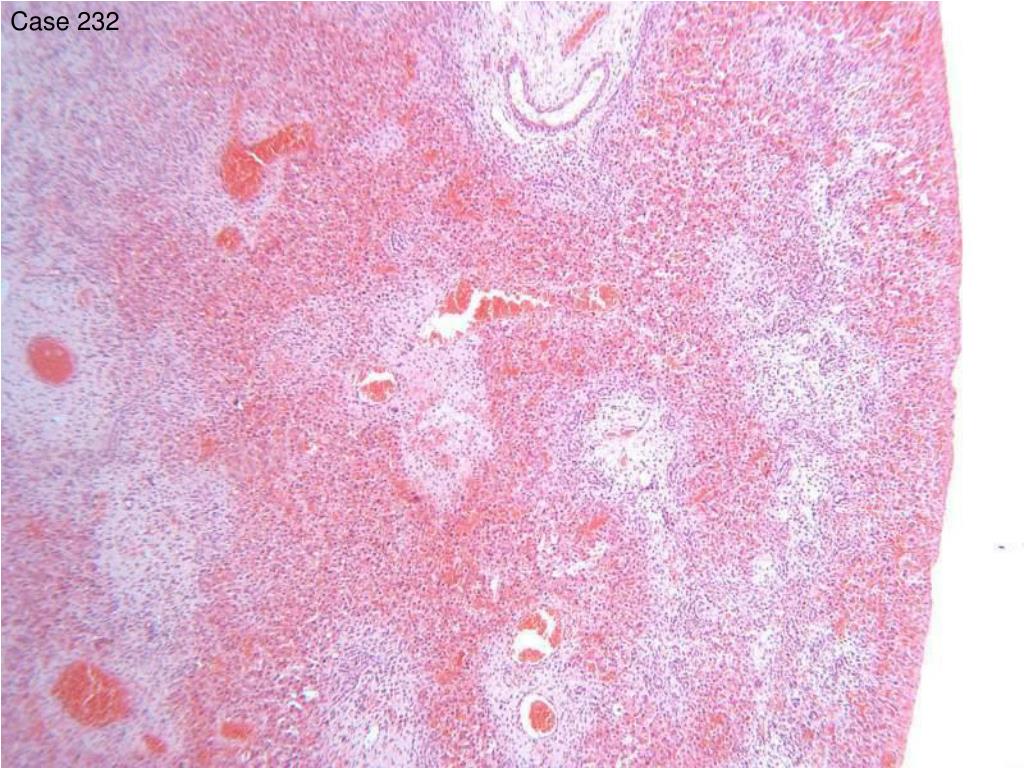

24. Case 232 • 4 day old female. Nodule stuck to side of diaphragm. • Crescent shaped piece of tan tissue, 23x8x8mm.

31. Case 232 • Comment: It was not clear whether this tissue was above or below the diaphragm. We presume that the portal changes of ductopenia, oedema, and ductular proliferation are a reflection of the absence of biliary drainage in this heterotopic portion of liver. • There is not an 80% consensus on the result. Many participants do not see paediatric cases therefore excluded from scoring.

32. Case 232 • Follow up: Dr Davies • This tissue was discovered attached to the liver by a narrow pedicle during surgical repair of a diaphragmatic hernia. It was initially thought to be sequestration ? of lung but found to be attached to liver at surgery. As far as is known, there was no problem with the rest of the liver.